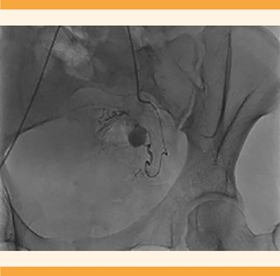

A su llegada al hospital de tercer nivel, la paciente se encontró estable y con sangrado en menor cantidad, pero persistente. Fue valorada por el radiólogo. Ante la sospecha de una malformación vascular se decidió proceder a la arteriografía pélvica en la que se objetivó una formación sacular, dependiente de la arteria hipogástrica izquierda, compatible con un pseudoaneurisma (Figuras 3 y 4) que justificaba la clínica de la paciente. Por ello, se decidió practicarle un cateterismo con embolización selectiva de la rama aferente del pseudoaneurisma, que concluyó sin contratiempos y se comprobó la ausencia de flujo a la formación aneurismática posterior a la embolización. Figura 5